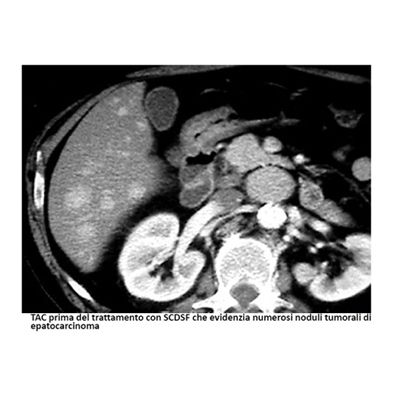

- Valutazione, terapie integrate e di supporto alle malattie tumorali del fegato (epatocarcinoma)